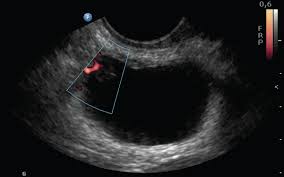

For bladder cancer, the stage is determined based on examining the sample removed during a turbt (see diagnosis) and finding out whether the cancer has spread to other parts of this type of bladder cancer often comes back after treatment, usually as another noninvasive cancer in the bladder. Cancer cells of this type look like the urothelial cells lining the inside of the bladder. Where should you go for care? As the number of cells increases, they form a tumor and eventually spread to other parts of the body. Cystoscopy is one of the most common procedures in which the bladder is introduced flexible tube with a camera. These start in the urothelial cells, which line. More than 90 percent of bladder cancers start in the cells that make up the innermost lining. Inhalation during cigarette smoking brings some of the. Treatment of bladder cancer depends on the stage of the cancer. There may be enough blood to change the color of the. Bladder cancer is one of the most common types of cancer that affect hundreds of thousands of adults every year. Bladder cancer occurs in the lining of the bladder. The bladder is a hollow organ in your lower abdomen that stores urine.

Cystoscopy is one of the most common procedures in which the bladder is introduced flexible tube with a camera.